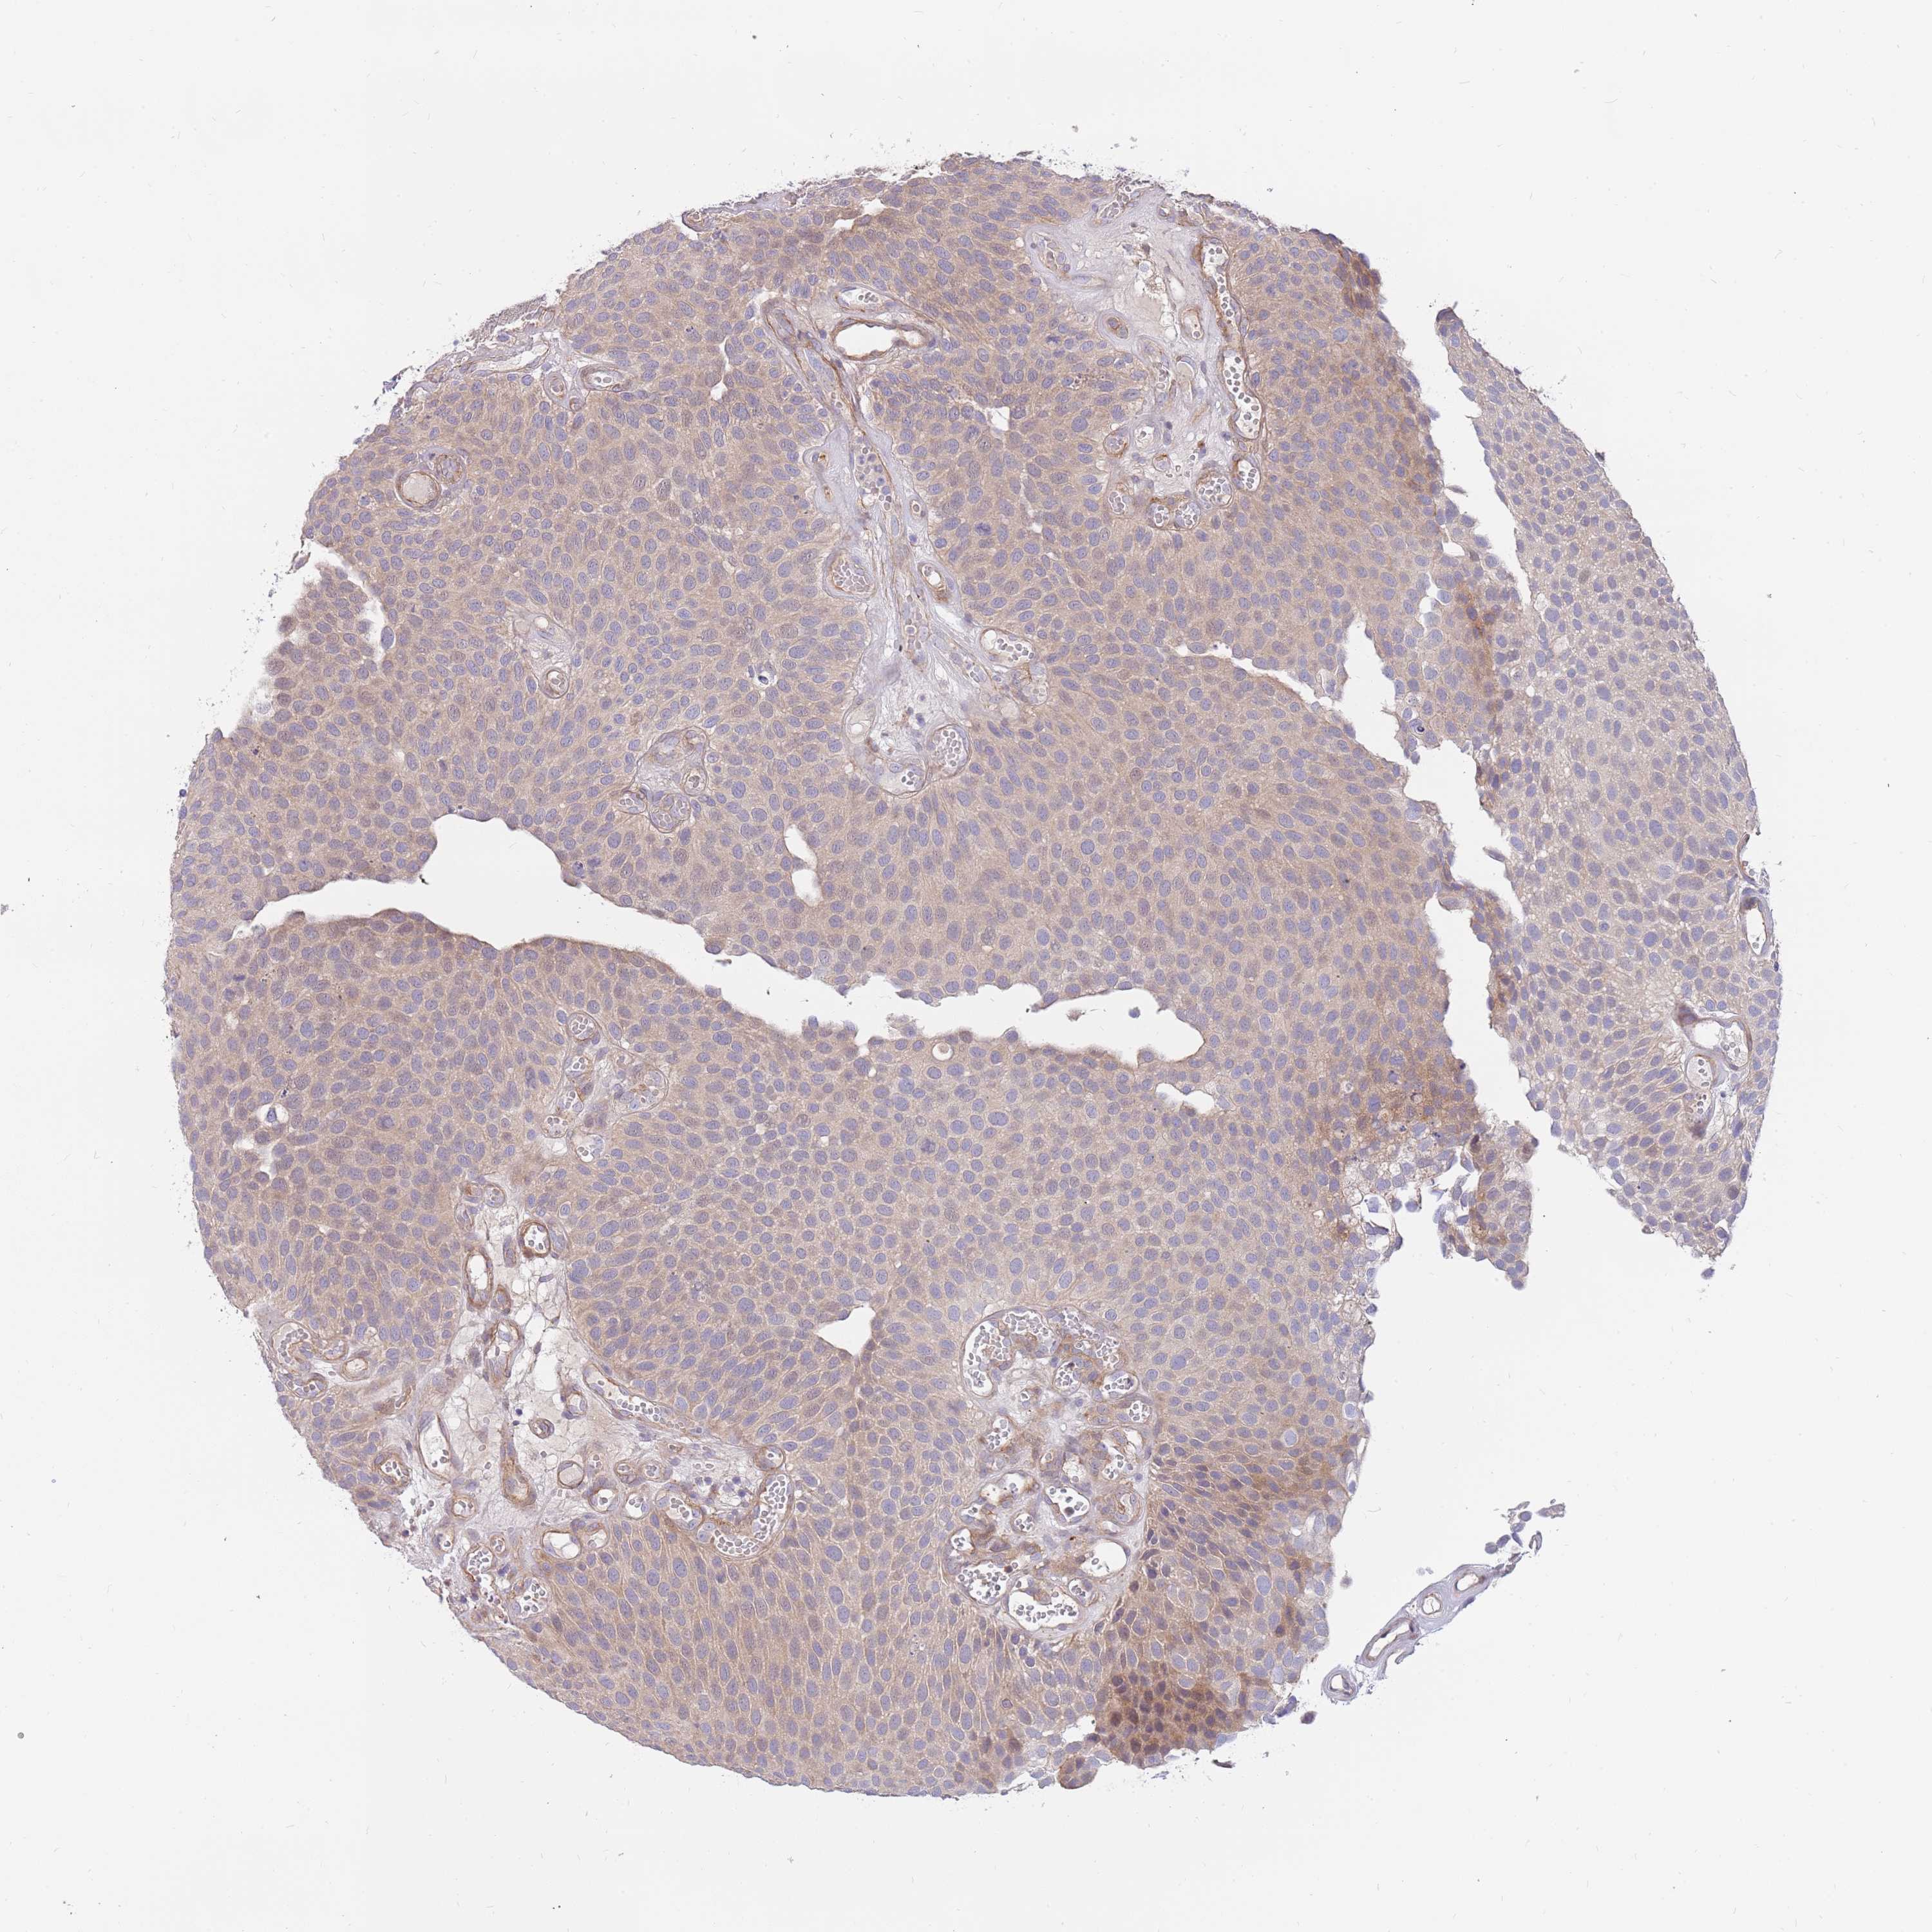

UROTHELIAL CANCER - Protein expressioni

A mouse-over function shows sample information and annotation data. Click on an image to view it in a full screen mode. Samples can be filtered based on level of antibody staining by selecting one or several of the following categories: high, medium, low and not detected. The assay and annotation is described here.

Note that samples used for immunohistochemistry by the Human Protein Atlas do not correspond to samples in the TCGA dataset.

Antibody stainingi

Antibody staining in the annotated cell types in the current human tissue is reported as not detected, low, medium, or high, based on conventional immunohistochemistry profiling in selected tissues. This score is based on the combination of the staining intensity and fraction of stained cells.

Each image is clickable and will lead to virtual microscopy that enables deeper exploration of all samples and also displays staining intensity scores, fraction scores and subcellular localization as well as patient and tissue information for each sample.

Antibody HPA041404

Antibody HPA048250

Staining

High

Medium

Low

Not detected

Intensity

Strong

Moderate

Weak

Negative

Quantity

>75%

75%-25%

<25%

None

Location

Nuclear

Cytoplasmic/membranous

Cytoplasmic/membranous,nuclear

Urothelial carcinoma, High grade

Urothelial carcinoma, Low grade